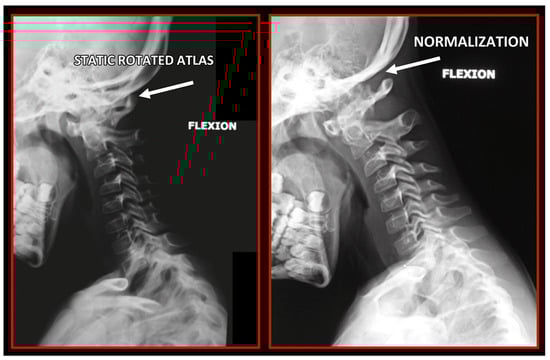

10.1. Neck X-ray

11.5. Axis and Atlas Derotation